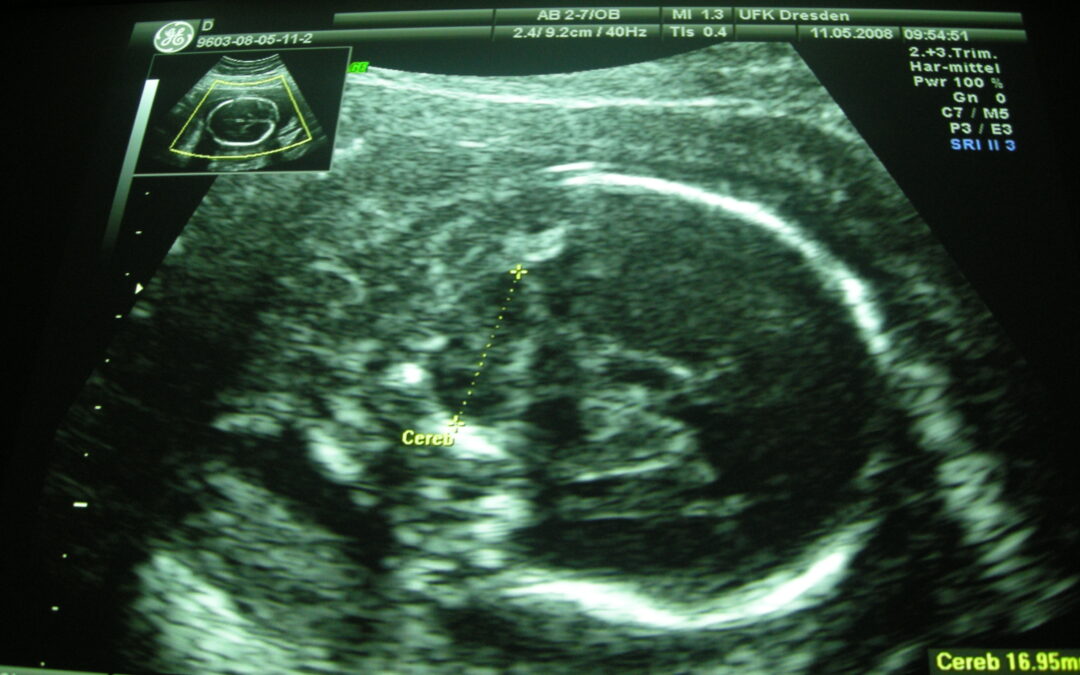

Imagen de cerebelo en la semana 18 de gestación.